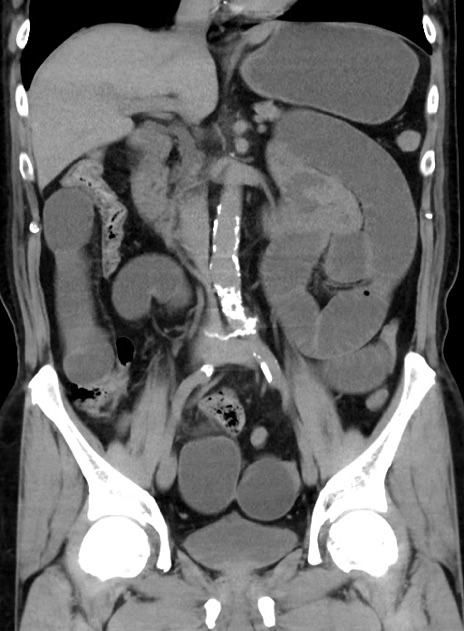

症例38(冠状断像)

【症例】70歳代 男性

【主訴】腹痛・嘔吐

【現病歴】昨晩より、嘔吐・腹痛あり。今朝になっても嘔吐あり。来院。

【既往歴】心臓バイパス手術、開腹胆摘、腸閉塞

【身体所見】BP 107/71mmHg、HR 116/min、腹部:平坦、軟、下腹部に軽度圧痛あり。反跳痛なし。

【データ】WBC 15100、CRP 0.32